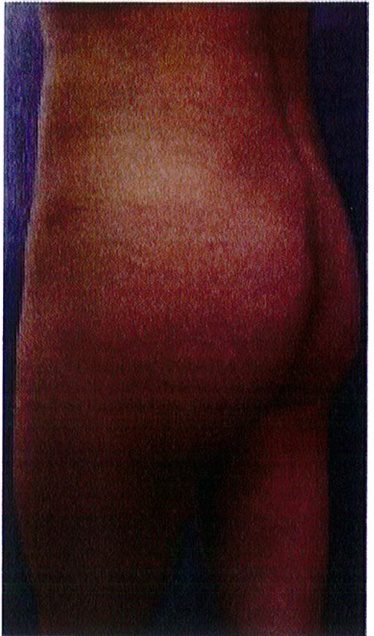

Hình. 21. (A) Hình anh trước và (B) và sau phẫu thuật làm đầy mông của bệnh nhân có vùng thắt lưng tương đối phẳng. Bệnh nhân được đặt khối im- plant dưới cân thế tích 330 mL ở hai bên.

Cuối cùng, một bệnh nhân 48 tuổi có vùng thắt lưng tương đối phẳng. Với tiền sử đã từng hút mỡ và hiện tại đang mong muốn được làm đầy mông để cải thiện hình thể phần thắt lưng (một cách tương đối). Hai khối implant mi- crotextured thể tích 300 mL được đặt ở dưới cân. Bệnh nhân được tiếp tục điều trị bằng liệu pháp siêu âm (dùng sóng siêu âm) sau phẫu thuật nhằm giảm phản ứng viêm tại chỗ. Sau phẫu thuật không ghi nhận biến chứng (Hình 21).